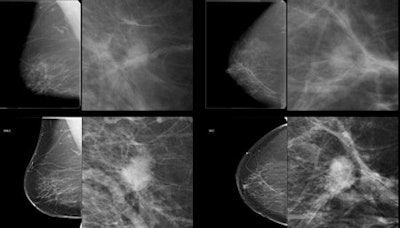

Subtle mass that was not recalled during screening, but detected on CAD. Top row: Exams that were not recalled during screening. Bottom row: Exams where lesion was detected in a later screening round. All images courtesy of Dr. Jaime Melendez.